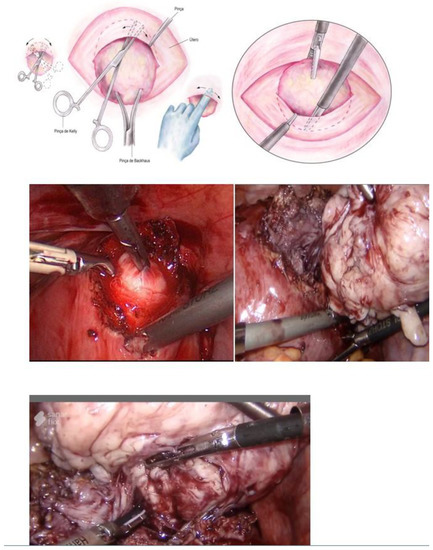

Myomectomy, whether laparotomic or laparoscopic, is a well-established procedure, widely performed with the goal of uterine preservation. In both approaches, the myomectomy technique is the same: incision of the serosa up to the pseudocapsule, identification of the myoma, traction and movement of the nodule, assistance in dissecting the plane of the pseudocapsule within the myometrium, and enucleation of the myoma from the uterine wall. This fibroid enucleation technique is known and performed by all gynecologists. When the pseudocapsule is reached, the chance of preserving the uterus will be greater, with less bleeding and less myometrial damage, which differs from adenomyosis resection, which does not have a pseudocapsule [21] (Figure 6).

Figure 6. Laparotomic and laparoscopic myomectomy preserving pseudocapsule.